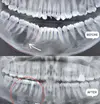

Fotoğraflar